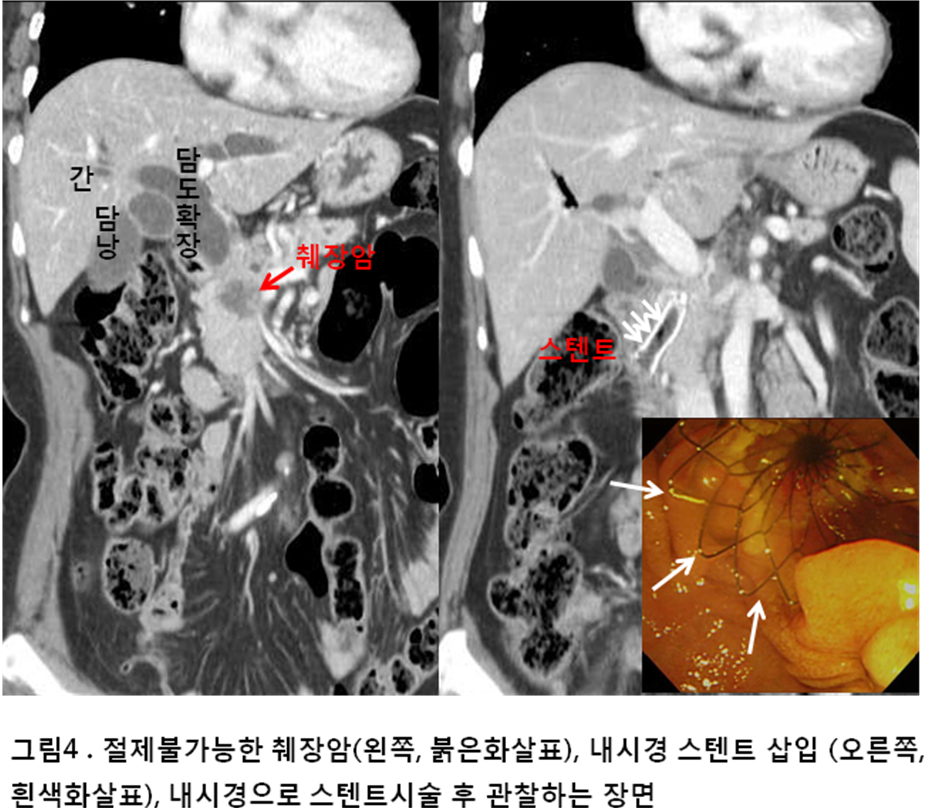

두 번째로 주목해야 할 증상은 황달입니다. 황달은 피부나 눈의 흰자위가 노랗게 변하는 증상으로, 간이나 췌장에 문제가 있을 때 나타날 수 있습니다. 췌장암이 발생하게 되면, 종양이 담관을 압박하여 담즙이 제대로 배출되지 않으면 황달이 생길 수 있습니다.

황달이 생기면 피부가 가렵거나 소변 색깔이 어두워지는 증상이 동반될 수 있습니다. 만약 이러한 증상이 나타난다면, 즉시 병원을 방문하여 검사를 받는 것이 필수입니다. 그동안의 생활 습관이나 건강 상태를 점검할 기회가 될 수 있습니다.